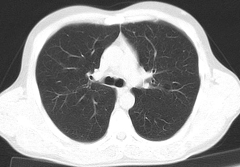

Томография легких - один из способов диагностики заболеваний легких. Проводят его с помощью кольцевидного рентгена, делающего снимки легких под разными углами. Большое распространение получила компьютерная томография, которая дает возможность оцифровать полученные снимки, предоставить для анализа многочисленные срезы легких.

С помощью томографии можно выявить хроническую эмболию, туберкулез, диффузные заболевания, рак легких (локализация опухолей, состояние лимфоузлов, наличие и распространенность метастаз), пневмонию, профессиональные заболевания, вызванные вдыханием кремниевых частиц, асбеста, кварца и т.п.